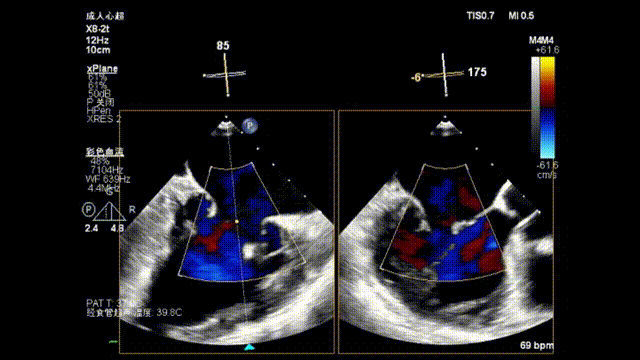

测量穿刺点距离二尖瓣环的位置,测量为4.35cm;沿着导丝置入可调弯导引导管,使其穿出穿刺点2cm左右

瓣上M/L和A/P调整瓣膜夹,在X-plane和3D下反复确认弹道和夹臂方向

瓣上M/L和A/P调整瓣膜夹,在X-plane进行超声确认(视频),进行弹道路径检查;